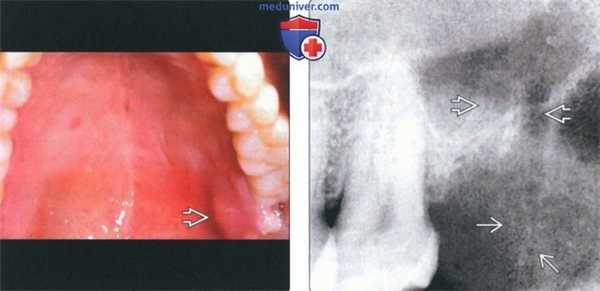

(Слева) На фотографии верхней челюсти определяется отек неба в области третьего моляра слева. Третий моляр удален, но заживление дефекта после удаления зуба не происходит.

(Справа) На периапикальной рентгенограмме у этого же пациента определяется дефект после удаления третьего моляра слева и мягкотканное образование с множественными включениями костной ткани, распространяющееся от дефекта в сторону зуба-антагониста. Была выполнена биопсия, подтвердился диагноз остеосаркомы.2. Рентгенография при остеосаркоме челюсти: